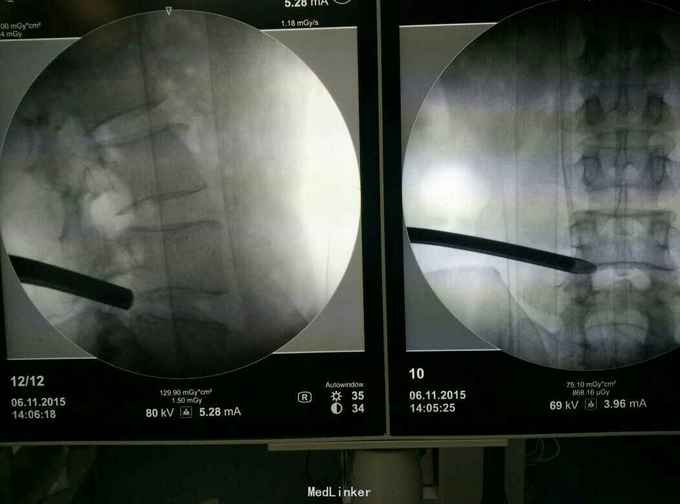

诊断:L45腰椎间盘脱出游离。 治疗:行侧路椎间孔镜手术。

术后症状缓解,左腿直腿抬高80度。此类患者,行侧路椎间孔镜有一定难度,但是侧路椎间孔镜创伤小,恢复快。各位大侠对这样的病例还有什么好的处理方案?